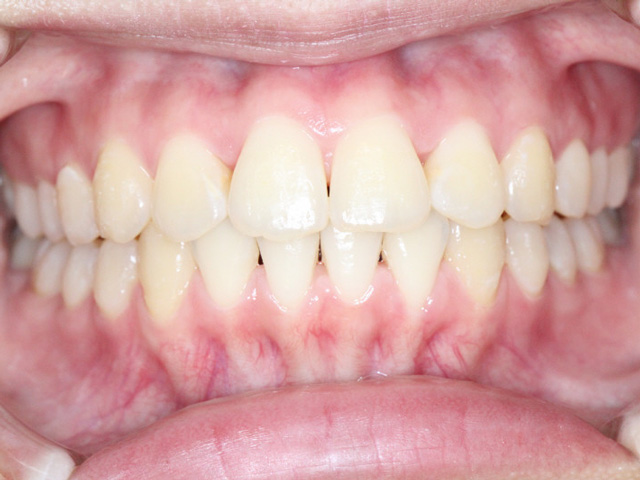

笑ったときに前歯が出ている、噛み合わせがズレている、歯が重なって生えてきている…。実はこれらは、成長とともに自然に治ることもあれば、逆に悪化してしまうケースもあります。

この時期に矯正治療を行うことは歯並びの改善だけではなく、骨格成長を活かすためとてもバランスのとれた顔貌(がんぼう)になり、見た目の改善に大きく寄与します。

小児矯正と大人の矯正の最大の違いは、成長を利用できるかどうかです。この貴重なタイミングを活かすことで、より自然で安定した歯並びを目指すことができます。

また顎の成長を正しく誘導することで、横顔のバランスが整い、自然で美しいフェイスラインになります。

大人の場合、顎の成長はすでに止まっているため歯を動かすことしかできません(但し、決してきれいな歯並び及び顔貌にできないという意味ではありません)。スペース不足を解消するため抜歯が必要になることがあります。一方で子どもの場合は成長途中にあるため、顎の成長発育を利用して歯を動かすことは様々なメリットを生み出します。